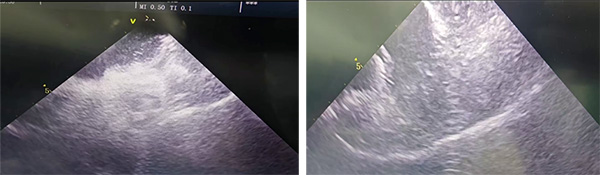

术前心脏超声结果示:左房增大,房间隔左向右分流影,分流束宽8-11mm

通过超声可见封堵器外盘形态良好,未见明显残余分流;可再行房间隔缺损封堵术。

房缺封堵器植入后推拉稳定,形态良好,通过经胸彩超未见残余分流,遂释放封堵器。